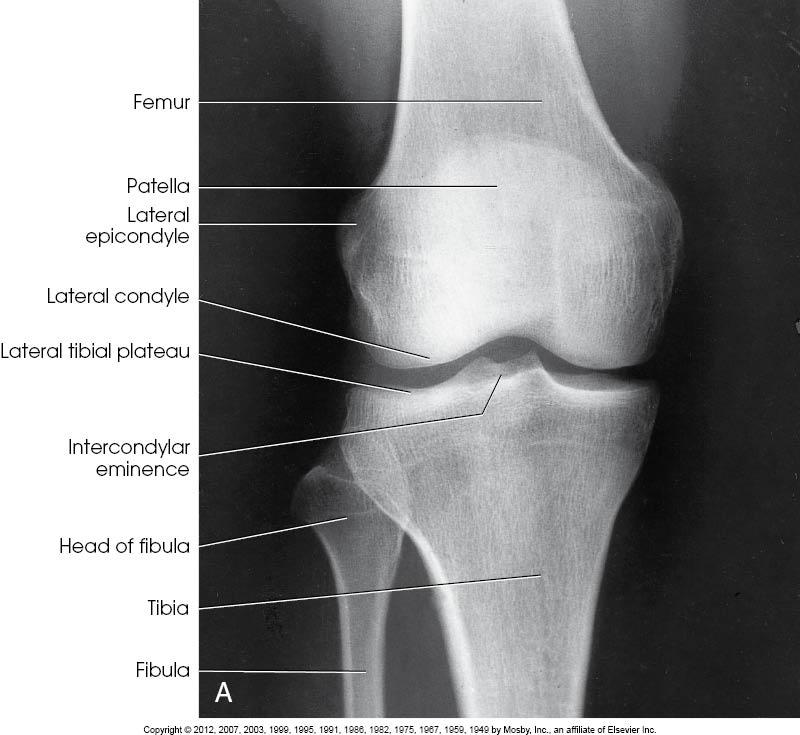

Structures

Shown

• Open knee joint

• Patella superimposed on

femur

• Soft tissue

AP of the Knee